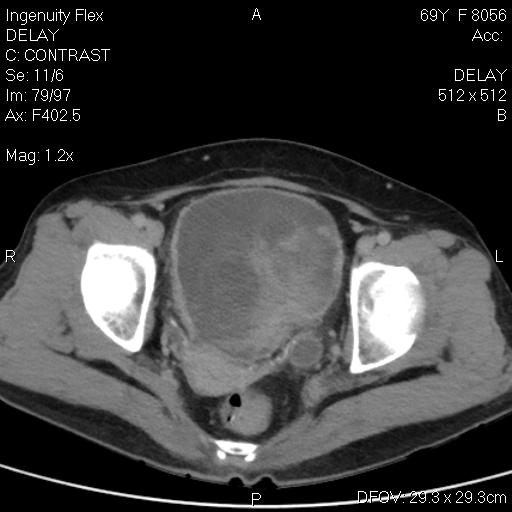

CT-ung thư cổ tử cung

CT-ung thư cổ tử cung 2

CT-ung thư cổ tử cung - di căn gan - tràn dịch màng phổi, ổ bụng

CT-ung thư nội mạc tử cung